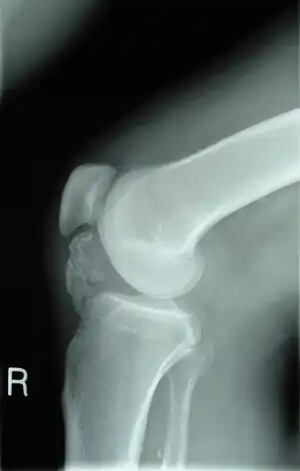

Osteochondroma arising from the thigh bone, near the knee

Osteochondroma arising from the large long bone of lower leg, near the knee